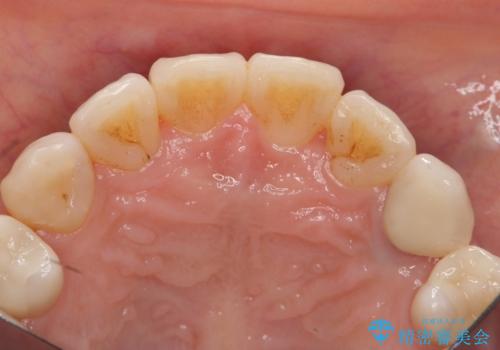

術後は計画通り歯ぐきの腫れが収まり、炎症に強い歯ぐきになりました。

左:虫歯を除去したところ。遠心が歯ぐきより深い状態です。中:そのままかぶせようとすると、遠心が歯ぐきが腫れやすい状態です。右:エクストリュージョンをしたことで、遠心の歯ぐきの腫れが収まっていることがわかります。

エクストリュージョンをしたことで、いくら歯磨きを頑張ってもどうしても腫れてしまう歯肉に対して、歯周囲組織の位置関係を変えることで根本的に解決しました。

今回は、単独1歯のエクストリュージョンを、マウスピースを使って、ご自身でゴムをかけていただき行ったのがポイントです。